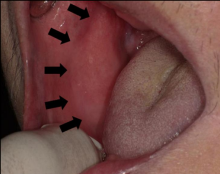

Khalid et al. [12] reported a 76-year-old Chinese man, who had attended the clinic with a manifestation of swelling over his right buccal mucosa with on and off pain and numbness at his right chin in December 2017. His symptoms had commenced two months preceding his attendance at the clinic. It was found upon his examination that clinically his buccal mucosa was smooth, and a well-defined firm mass could be palpated over his normal overlying buccal mucosa (see Figure 1). He was completely edentulous with no restriction of his mouth opening.

Figure 1: Intraoral photograph showing smooth, well-defined, firm mass over the right buccal mucosa with normal overlying mucosa. Reproduced from: [12] Under the Creative Commons Attribution License.